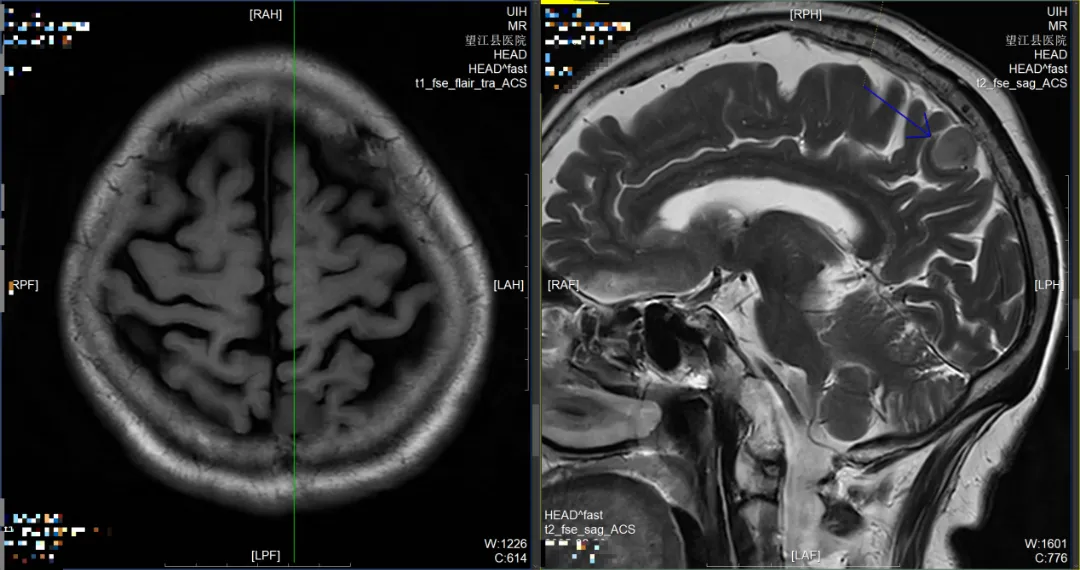

無癥狀腫瘤:MRI軟組織對比度極佳,結(jié)合動態(tài)增強(qiáng)技術(shù),可發(fā)現(xiàn)垂體微腺瘤(<1cm)、聽神經(jīng)瘤等緩慢生長的腫瘤,甚至能鑒別乳腺、前列腺等部位的早期惡性病變,實(shí)現(xiàn)“早于癥狀的診斷”。

左側(cè)頂部小腦膜瘤